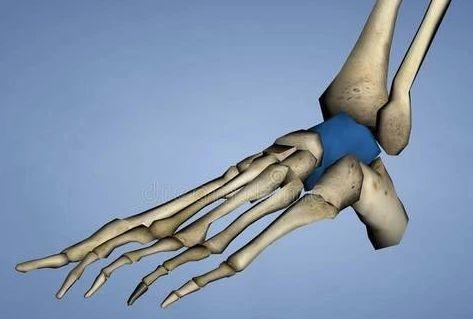

El astrágalo se encuentra en la parte superior del arco del pie, dentro del punto del tobillo. Como bisagra que conecta la pierna y el pie, las articulaciones del astrágalo tibial y subastragalino proporcionan la movilidad principal del pie trasero. El astrágalo es el segundo hueso tarsal más grande del cuerpo humano. Aproximadamente dos tercios de su superficie están cubiertos por cartílago articular. Es el único hueso del cuerpo sin unión tendinosa. Su estabilidad se mantiene principalmente por la estructura ósea circundante, la articulación tejido de la cápsula y del ligamento. La cabeza del astrágalo está articulada a la parte anterior del escafoides y está sostenida por el ligamento del escafoides (resorte) del calcáneo. La superficie inferior del astrágalo tiene 3 superficies articulares (anterior, media y posterior) conectadas a la superficie superior del calcáneo. Hay un tubo tarsiano entre la superficie superior del calcáneo y la superficie inferior del astrágalo, que se abre lateralmente para formar el seno del tarso.